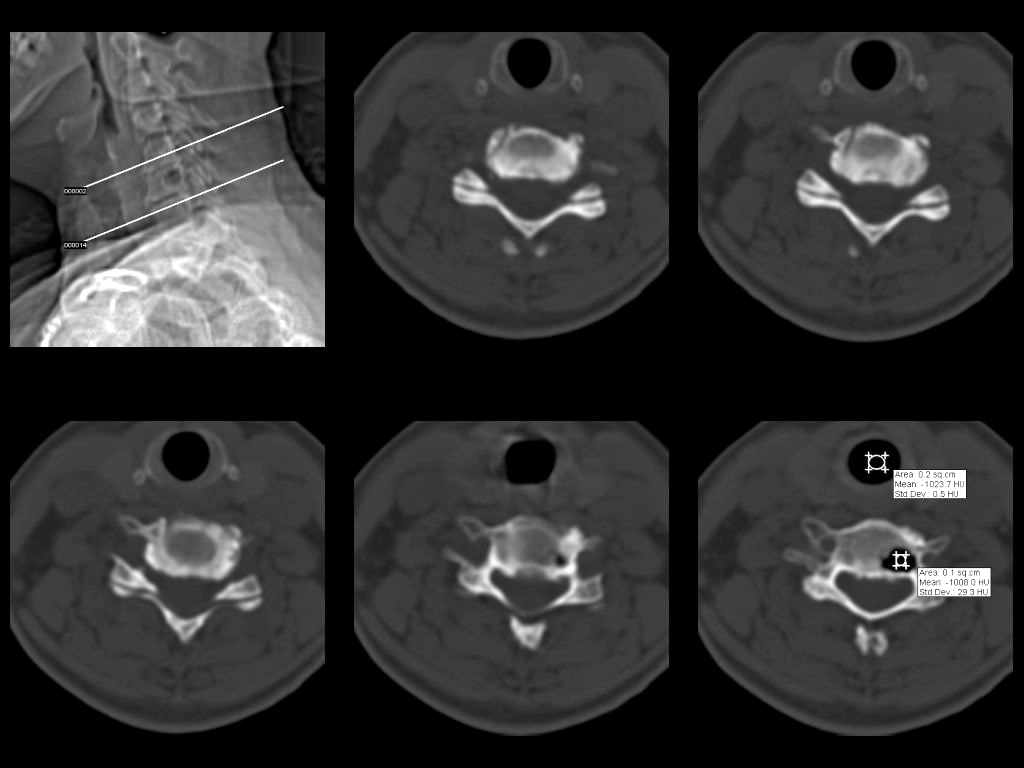

У женщины 49 лет, при рентгенографии шейного отдела в теле С6 выявлен участок деструкции.Часть N1 Больная находилась в неврологическом отделении с диагнозом энцефалопатия. Была проведена КТ тела С6, 26.12.2002 выявлен участок деструкции 0,9х1,2 см, плотность участка составляет -1022 ед.Н. аналогичная плотности воздуха в трахее.Возникает вопрос что это? Метастаз, киста,или какой то вредный анаэроб грызет тело позвонка?Через пол года 03.06.2003 произведено повторное исследование. Отмечается отрицательная динамика. Участок деструкции увеличился в размерах, увеличелась площадь разрушения задней поверхности тела С6.

Наличие выраженных дистрофических изменений, а также сообщение полости в теле позвонка С6 с полостью межпозвонкового диска в сегменте С5-С6, а также наличие газа в полости межпозвонкового диска С5-С6 спереди, на границе фиброзного кольца и пульпозного ядра (3-й слева срез в нижнем ряду на второй из представленных КТ) делает диагноз остеохондроза, осложненного вакуум-феноменом и прорывом газа в полость тела позвонка с формированием воздушной кисты (пневмкисты) несомненным.

Размеры за 2002 год 1,2х0,9х1,2 мм

за 2003 1,3х0,9х1,2 мм. Но контур деструкции стал более неровный и внедрение в дужку С6 увеличелось.

Характер процесса не вполне ясен. Учитывая скопление газа на фоне тела

позвонка, с наибольшей вероятностью - "вакуум-феномен" в следствии

дегенерации межпозвонкового диска. Наложение газа на образование в теле

позвонка (гемангиома?) создает затруднение в диагностике (по-видимому

сочетание двух процессов). Желательно МРТ исследование. Если возможно,